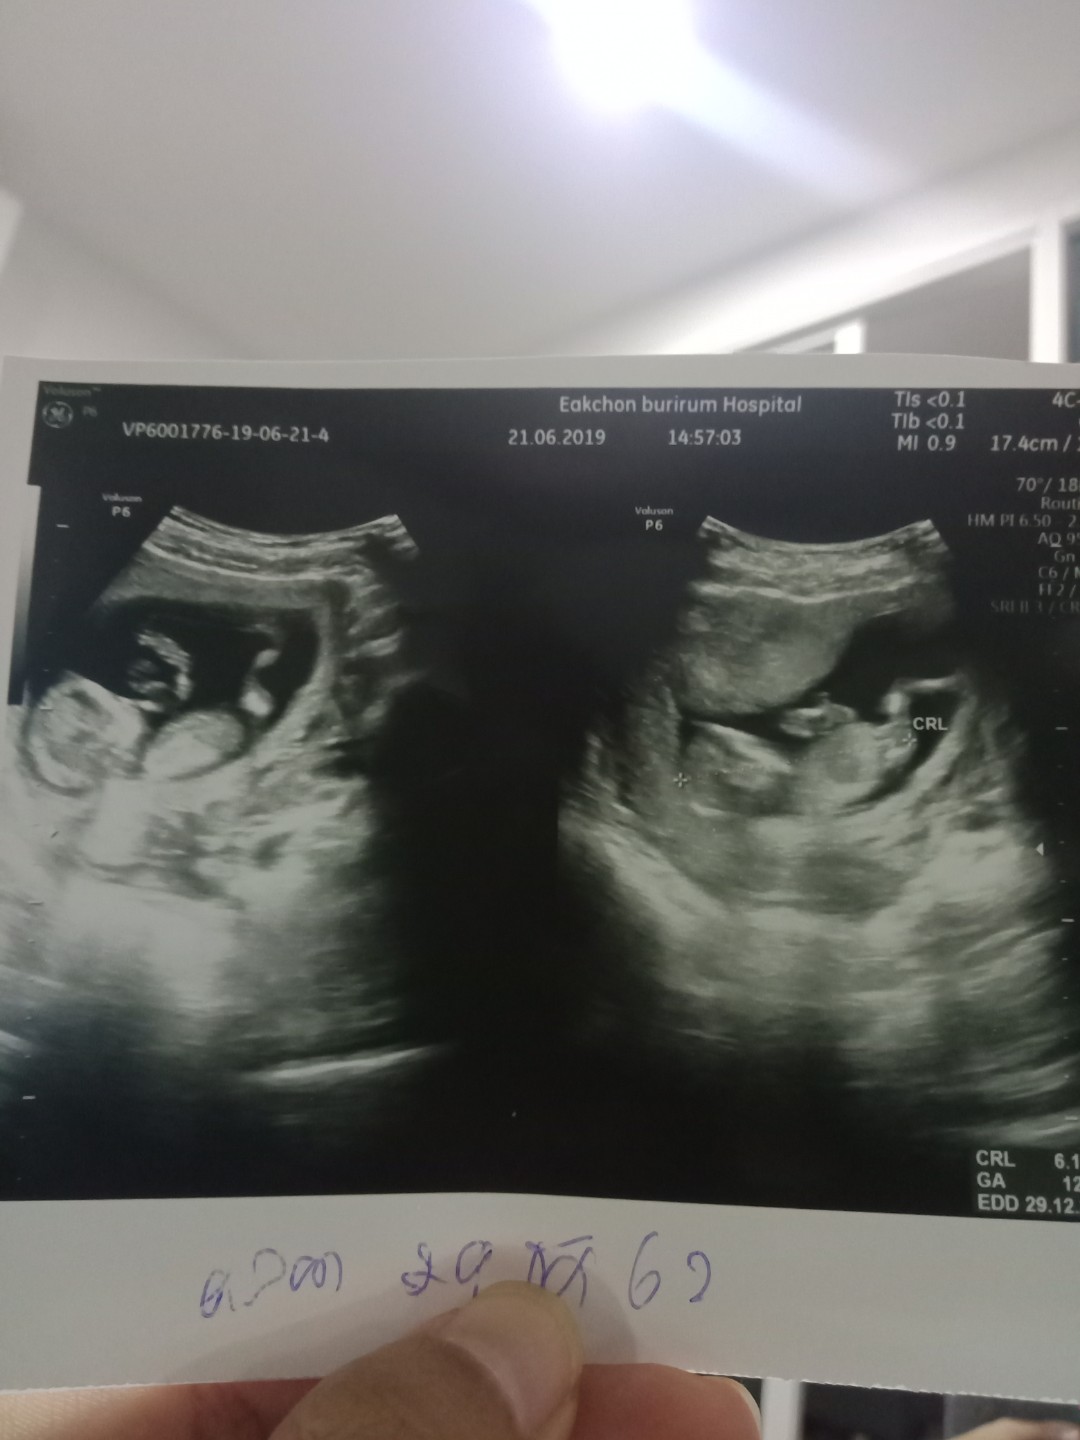

12w

Post reply image